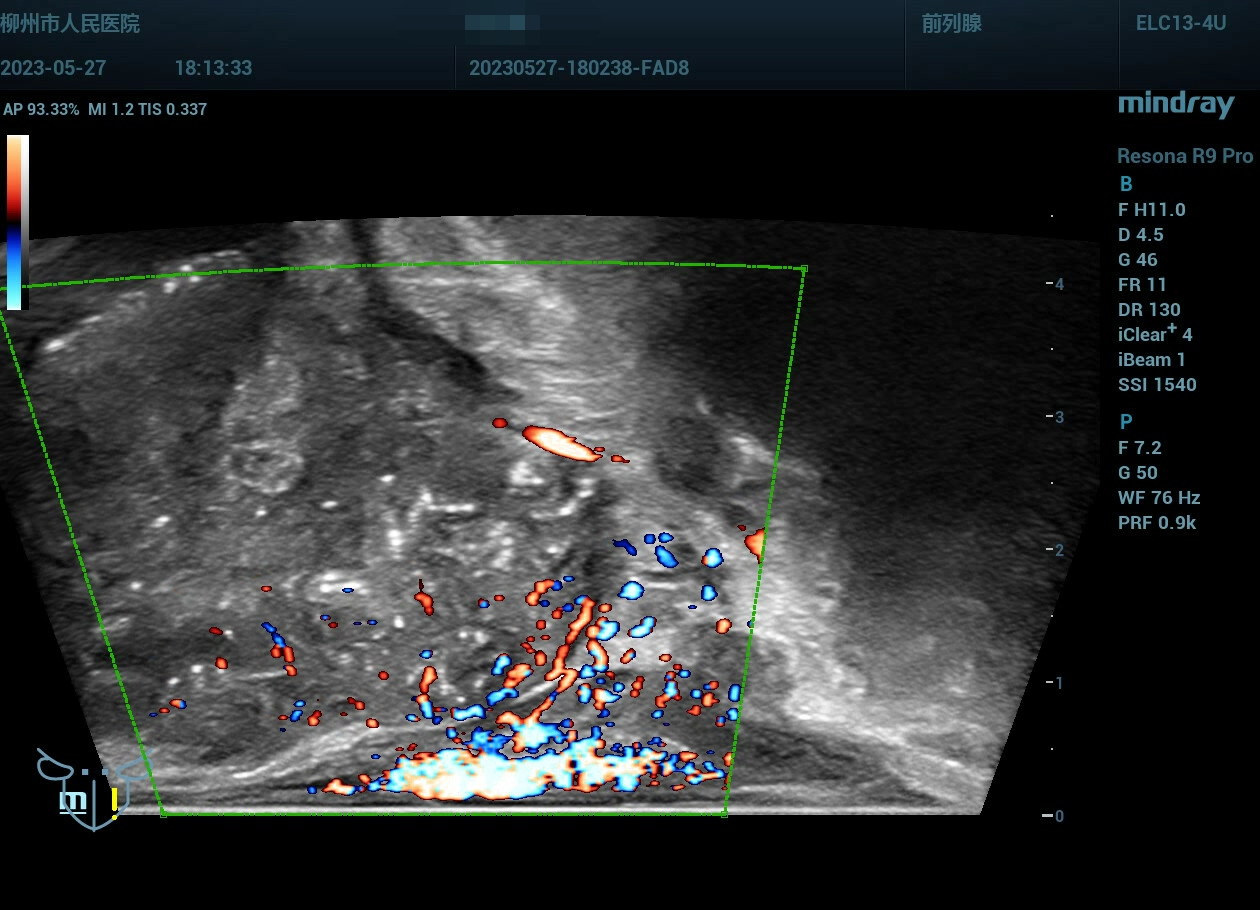

经会阴前列腺穿刺,病例实操(前列腺癌),柳州市人民医院,2023年

老年男性

经会阴前列腺穿刺,病例实操(前列腺癌),柳州市人民医院,2023年-主页丨今日超声